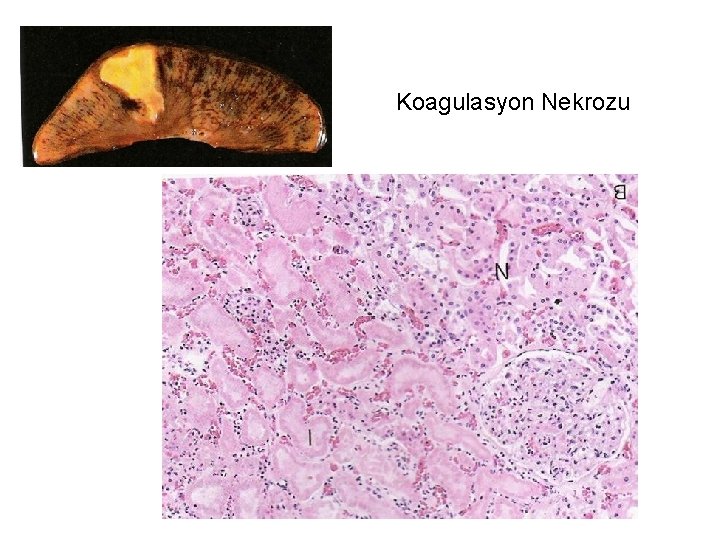

Nekroz tipleri: • Koagülasyon nekrozu (Beyin dışı dokularda, hipoksiye bağlı hücre ölümünün karakteristik görüntüsüdür. ) Doku çatısı bir süre de olsa korunur. • Likefaksiyon nekrozu (Beyinde hipoksiye bağlı hücre ölümünün karakteristik görüntüsüdür + Enfeksiyöz durumlarda) • Kazeifikasyon nekrozu (Ör: tüberküloz) • Yağ nekrozu (yağ dokusunu oluşturan hücrelerin ölümündeki görüntüdür. )

Koagulasyon Nekrozu